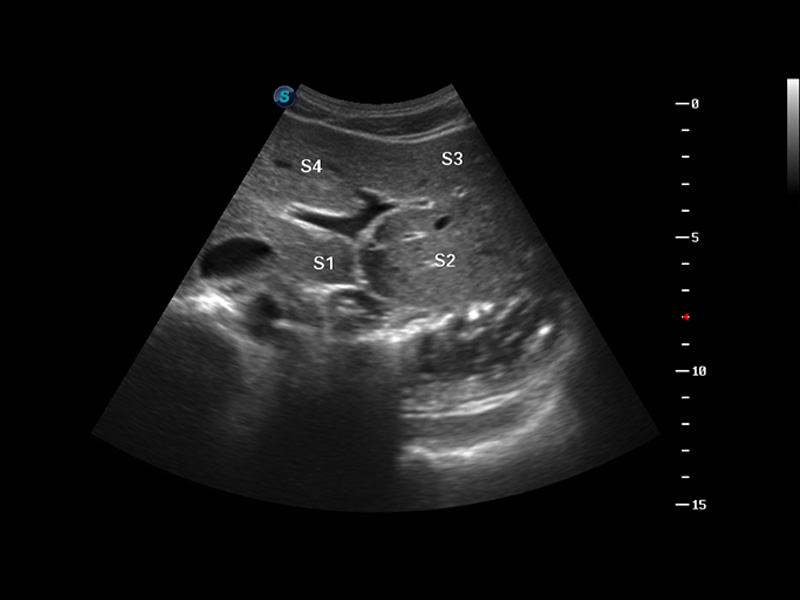

S8 EXP便携式彩色多普勒超声诊断仪是银河集团官网研发的高端全身应用型便携彩超。高通道的VIS平台融合可视化(Visual)、智能化(Intelligent)和人性化(Smart)的特点,配以银河集团官网自主研发生产的探头大家族,使您能够快速、准确的获得病人信息,提高工作效率的同时减轻疲劳。

3D/4D成像